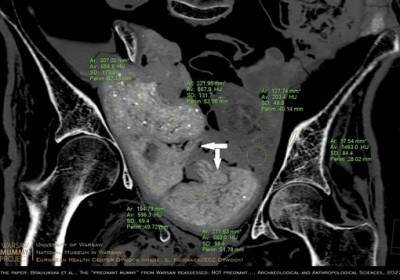

warszawska mumia

Mumia egipska z Warszawy nie była w ciąży - w jej miednicy znajdują się... pakunki

Nie płód, ale kilka zawiniątek znajduje się w miednicy mumii kobiety prezentowanej w Muzeum Narodowym w Warszawie - dowodzi zespół naukowców. W jednym… Czytaj więcej